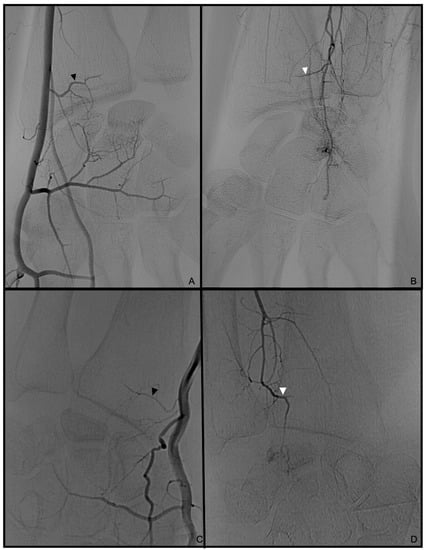

3.1. Palmar Radiocarpal Artery and Palmar Radiocarpal Arch (PRCA)

3.2. Dorsal Carpal Branch of the Ulnar Artery (DCBUA)

3.3. Anterior Interosseous Artery (AIA)